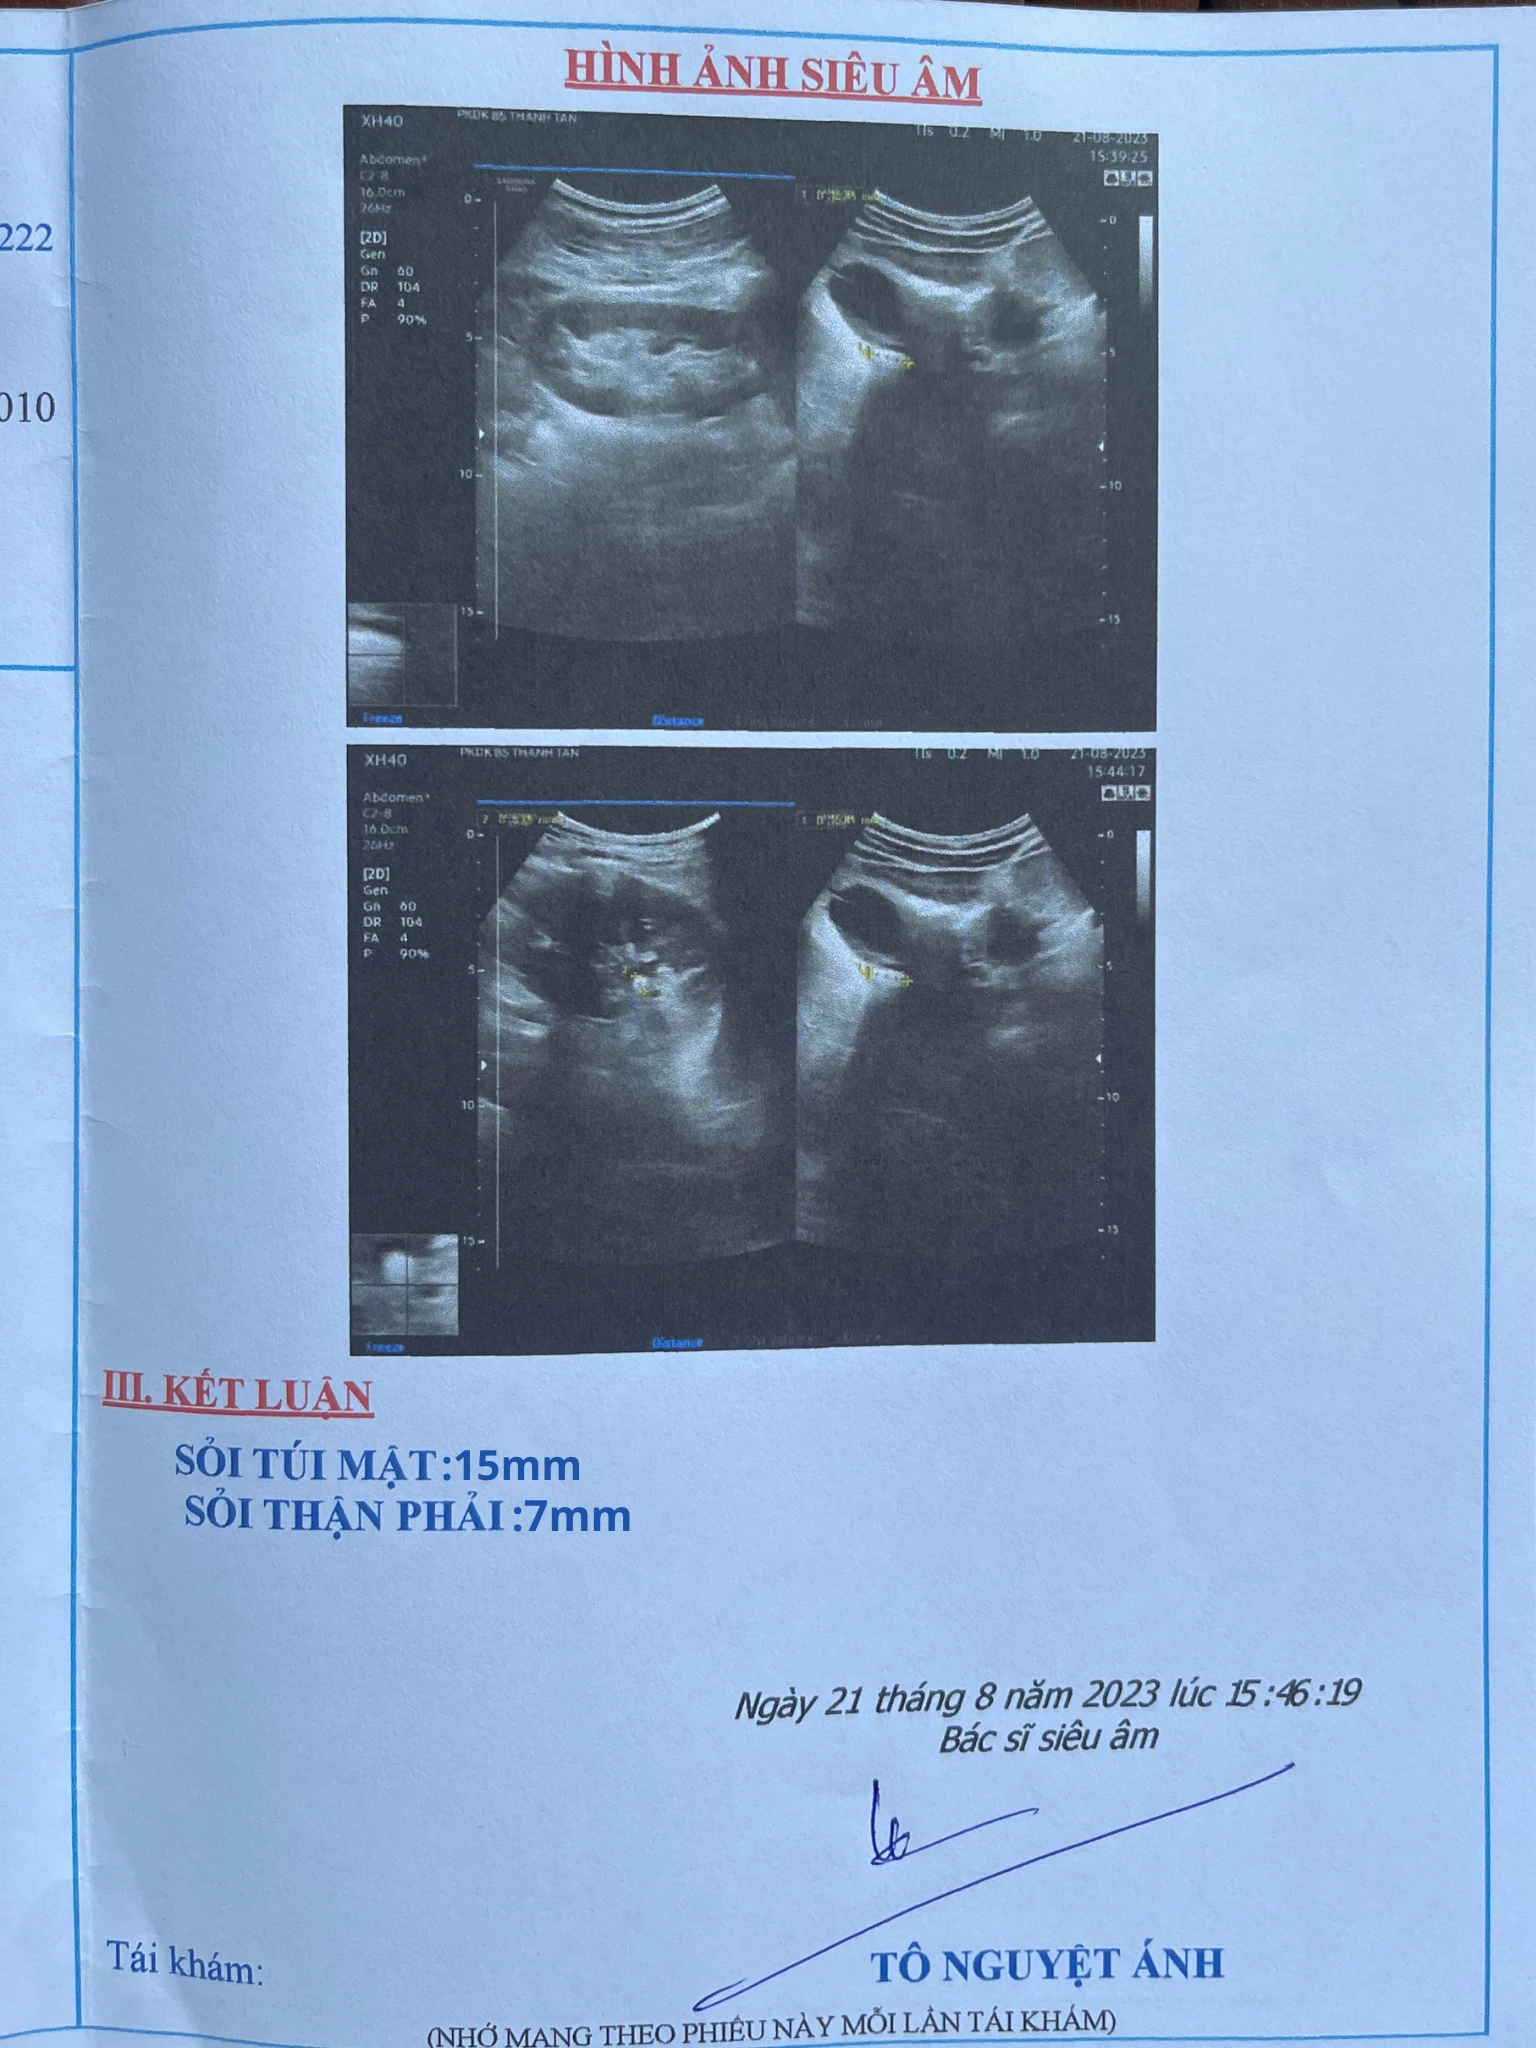

“Đau quá không chịu được nên tôi đi khám tại Bệnh viện Đa khoa Gò Dầu. Bác sĩ chẩn đoán tôi mắc sỏi túi mật 15 mm và sỏi thận 7 mm. Sỏi kích thước lớn nên bác sĩ khuyên tôi nên sớm phẫu thuật cắt túi mật. Tôi cũng suy nghĩ đắn đo lắm nhưng trong nhà tôi có người từng phẫu thuật rồi. Vết mổ ghê lắm mà nó vẫn cứ bị lại đấy có hết được đâu” - chú Văn Anh chia sẻ.

2.png

Chú Văn Anh bất ngờ phát hiện ra sỏi túi mật 15 mm khi kích thước đã lớn.